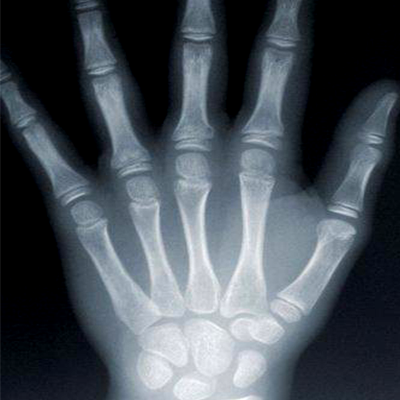

Un rayos X (radiografía) es un examen médico no invasivo que ayuda a los médicos a diagnosticar y tratar las condiciones médicas. La toma de imágenes con rayos X supone la exposición de una parte del cuerpo a una pequeña dosis de radiación ionizante para producir imágenes del interior del cuerpo. Los rayos X son la forma más antigua y de uso más frecuente para producir imágenes médicas.

Una radiografía ósea toma imágenes de cualquier hueso en el cuerpo, incluyendo la mano, muñeca, brazo, codo, hombro, columna, pelvis, cadera, muslo, rodilla, pierna (espinilla), tobillo o pie.